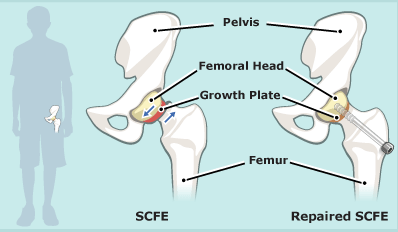

2. As ‘n groeiende kind kla van knie- of bobeenpyn, en daar is nie fout by die knie of bobeen nie, moet die kind se heup ondersoek word, want die bobeen-kop wat in die heuppotjie moet pas, kan verbrokkel, of selfs afbreek.

Lees meer: https://orthoinfo.aaos.org/en/diseases–conditions/slipped-capital-femoral-epiphysis-scfe